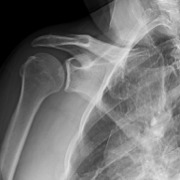

This 48-year-old male is a right hand dominant, nonsmoker with an active lifestyle. This patient presented with excellent range of motion and passing inactive range. Upon examination, strength presented at 5/5 rotator cuff, mild tenderness over the proximal long head of the biceps, but positive for subacromial impingement testing. Imaging revealed a skeletally mature individual with an intact glenohumeral joint space without signs of osteoarthritis and an intact acromial-humeral height distance (Figures 1-3).

Rotator cuff tears are one of the top causes of concerns seen by orthopedists. Over 1 million rotator cuff repairs are performed in the United States each year (“Orthopedic Soft Tissue Repair Market: Global Industry Analysis, Size, Share, Growth, Trends & Forecast, 2015-2030” 2022). Studies have found that up to 94% of large and massive tear rotator cuff repairs fail, with the majority failing as early as six months (Galatz et al. 2004; Iannotti et al. 2013). Symptoms are variable and can include nighttime pain, decreased strength, and difficulty performing daily activities. Initial diagnosis may include a physical exam with x-ray to assess the level of osteoarthritis, co-commitment fractures, and “high-riding” of the humeral head indicating advanced rotator cuff arthropathy. Furthermore, advanced imaging may be obtained using MRI or CT Arthrogram. Treatment may vary depending on tear size, fatty degeneration, muscle atrophy, type of tendon tear, and the level of retraction of the rotator cuff.